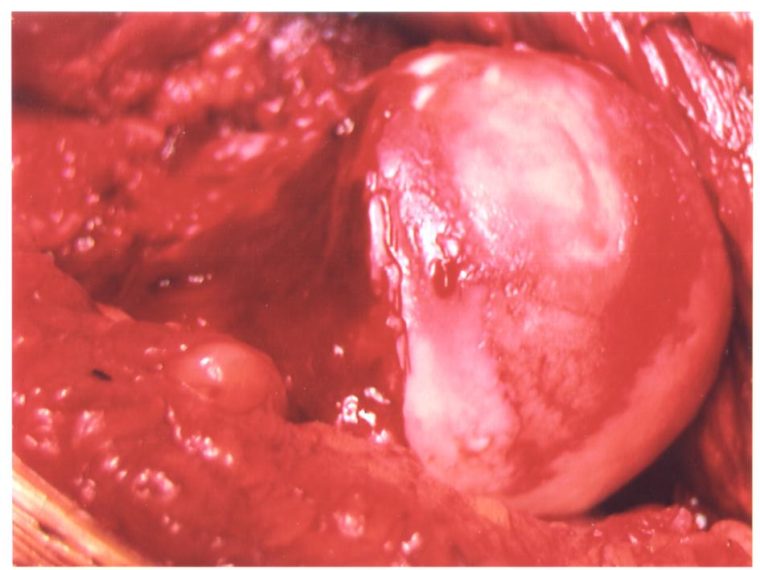

Anterior cam deformity of the left hip seen after surgical dislocation

Anterior cam deformity of the left hip seen after surgical dislocation.